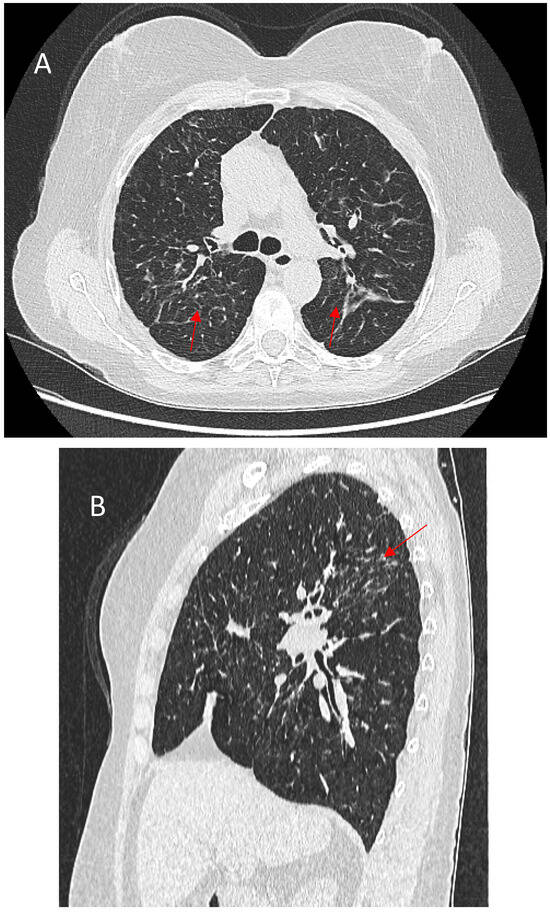

Figure 1

Background: Hypersensitivity pneumonitis (HP) is an interstitial lung disease (ILD) caused by repeated exposure to inhaled antigens in susceptible subjects. High-resolution computed tomography (HRCT) of the lungs is the leading diagnostic method for ILDs, but in some cases HRCT findings are not sufficient to distinguish HP and other ILDs, particularly, fibrotic HP (fHP) and usual interstitial pneumonia (UIP). Objective: The aim of this study was to develop HRCT criteria to diagnose fHP in patients with a UIP-like pattern. Methods: In this retrospective study, we analyzed HRCT scans of patients with fHP and a UIP-like pattern who underwent lung biopsy, and patients with idiopathic pulmonary fibrosis (IPF) and a UIP pattern in HRCT. Results: We included 51 patients with confirmed fHP and 24 patients with IPF/UIP in the analysis. IPF/UIP patients were older, were prevalently males, and did not have any systemic autoimmune diseases or risk factors for other ILDs. fHP patients were younger, with an equal number of males and females, and were more likely to be exposed to environmental antigens. HRCT abnormalities in the fHP group predominated in the lower lung areas or were diffuse in axial scans, whereas IPF/UIP patients mostly demonstrated a diffuse craniocaudal distribution and subpleural axial predominance. Centrilobular nodules and mosaic attenuation were present significantly more often in the fHP group; honeycombing, traction bronchiectasis, and emphysema prevailed in IPF/UIP patients. In the logistic regression analysis, patients with fHP and IPF/UIP differed in the presence of centrilobular nodules, honeycombing, and in both craniocaudal and axial distributions of HRCT abnormalities. In the ROC analysis, the combination of centrilobular nodules, honeycombing, and diffuse axial and craniocaudal distributions can predict the diagnosis of fHP (AUC, 0.953 ± 0.022; 95%CI, 0.910–0.995; p < 0.001). Mosaic attenuation and reticulation did not change the probability of fHP. Conclusions: The most significant HRCT features of fHP compared to the UIP pattern were centrilobular nodules, honeycombing, and a diffuse axial and craniocaudal distribution of abnormal findings. Reticulation, mosaic attenuation, and GGO do not increase the probability of fHP. Full article